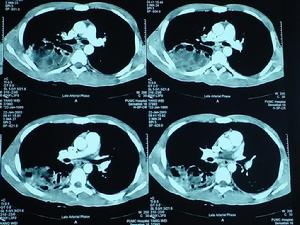

3、B 超檢查:B超對胃石診斷有一定幫助。通常囑患者飲水500~1000ml,坐位或半臥位檢查,可見到胃內有界限清晰的強回聲團塊影像,浮於水上層,並可隨體位變化或胃的蠕動而改變位置。